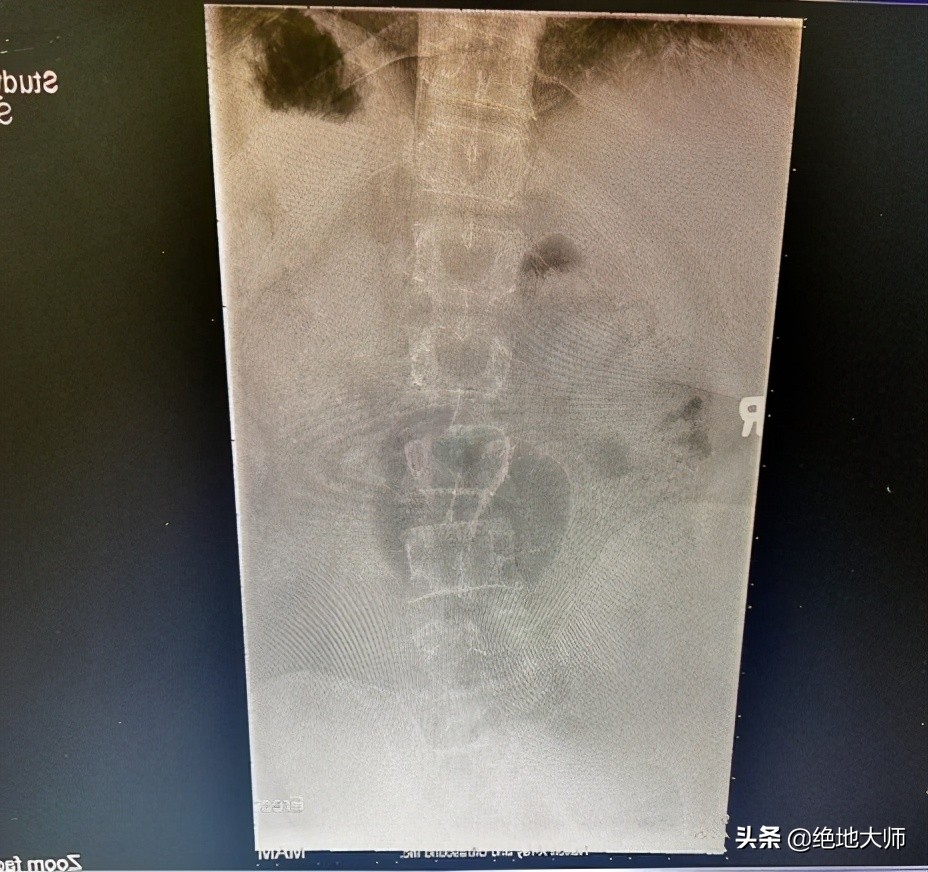

5. Structural leg length – spinal effects 结构性腿长 – 脊柱影响

左侧骨盆下降,鞋垫上推使骨盆水平。